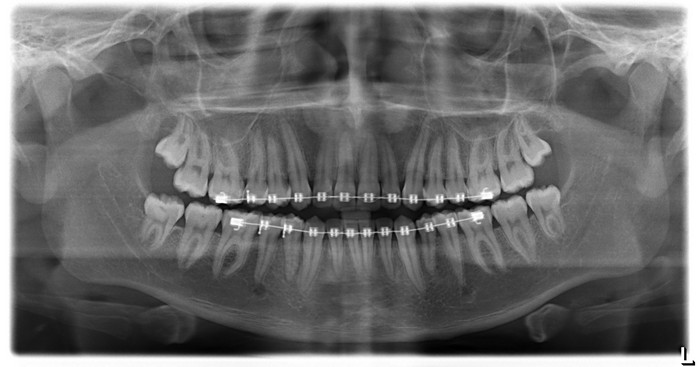

Sistemas y medios de diagnóstico de radiología digital para odontólogos, especialistas y subespecialistas en estética, ortodoncia, endodoncia, cirugía maxilar y maxilofacial, cráneo y cara, y odontología general Modelos maxilares testigos y de trabajo, fotografía clínica y diagnóstica para odontólogos generales.

En las siguientes imagenes encontrará información útil sobre la anatomía que se puede observar en una radiografía panoramica

Click sobre la imagen para ampliar